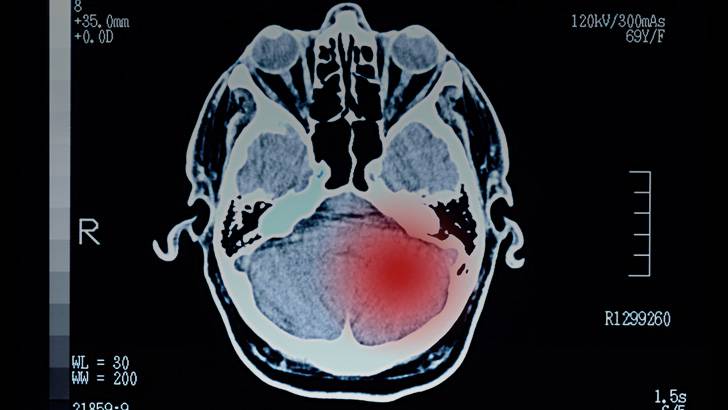

Brain metastases are common in patients with advanced melanoma and are a leading cause of cancer-related death. However, little is known as to why melanoma spreads to the brain, but new research from Columbia University may provide some answers. To discuss this recent discovery, Dr. Andrew Wilner is joined by Dr. Benjamin Izar, Assistant Professor of Medicine at Columbia University Vagelos College of Physicians and Surgeons.

Brain metastases are common in patients with advanced melanoma and are a leading cause of cancer-related death. Little is known as to why melanoma spreads to the brain, but new research from Columbia University that looks at the cells inside melanoma brain metastases may provide some answers.